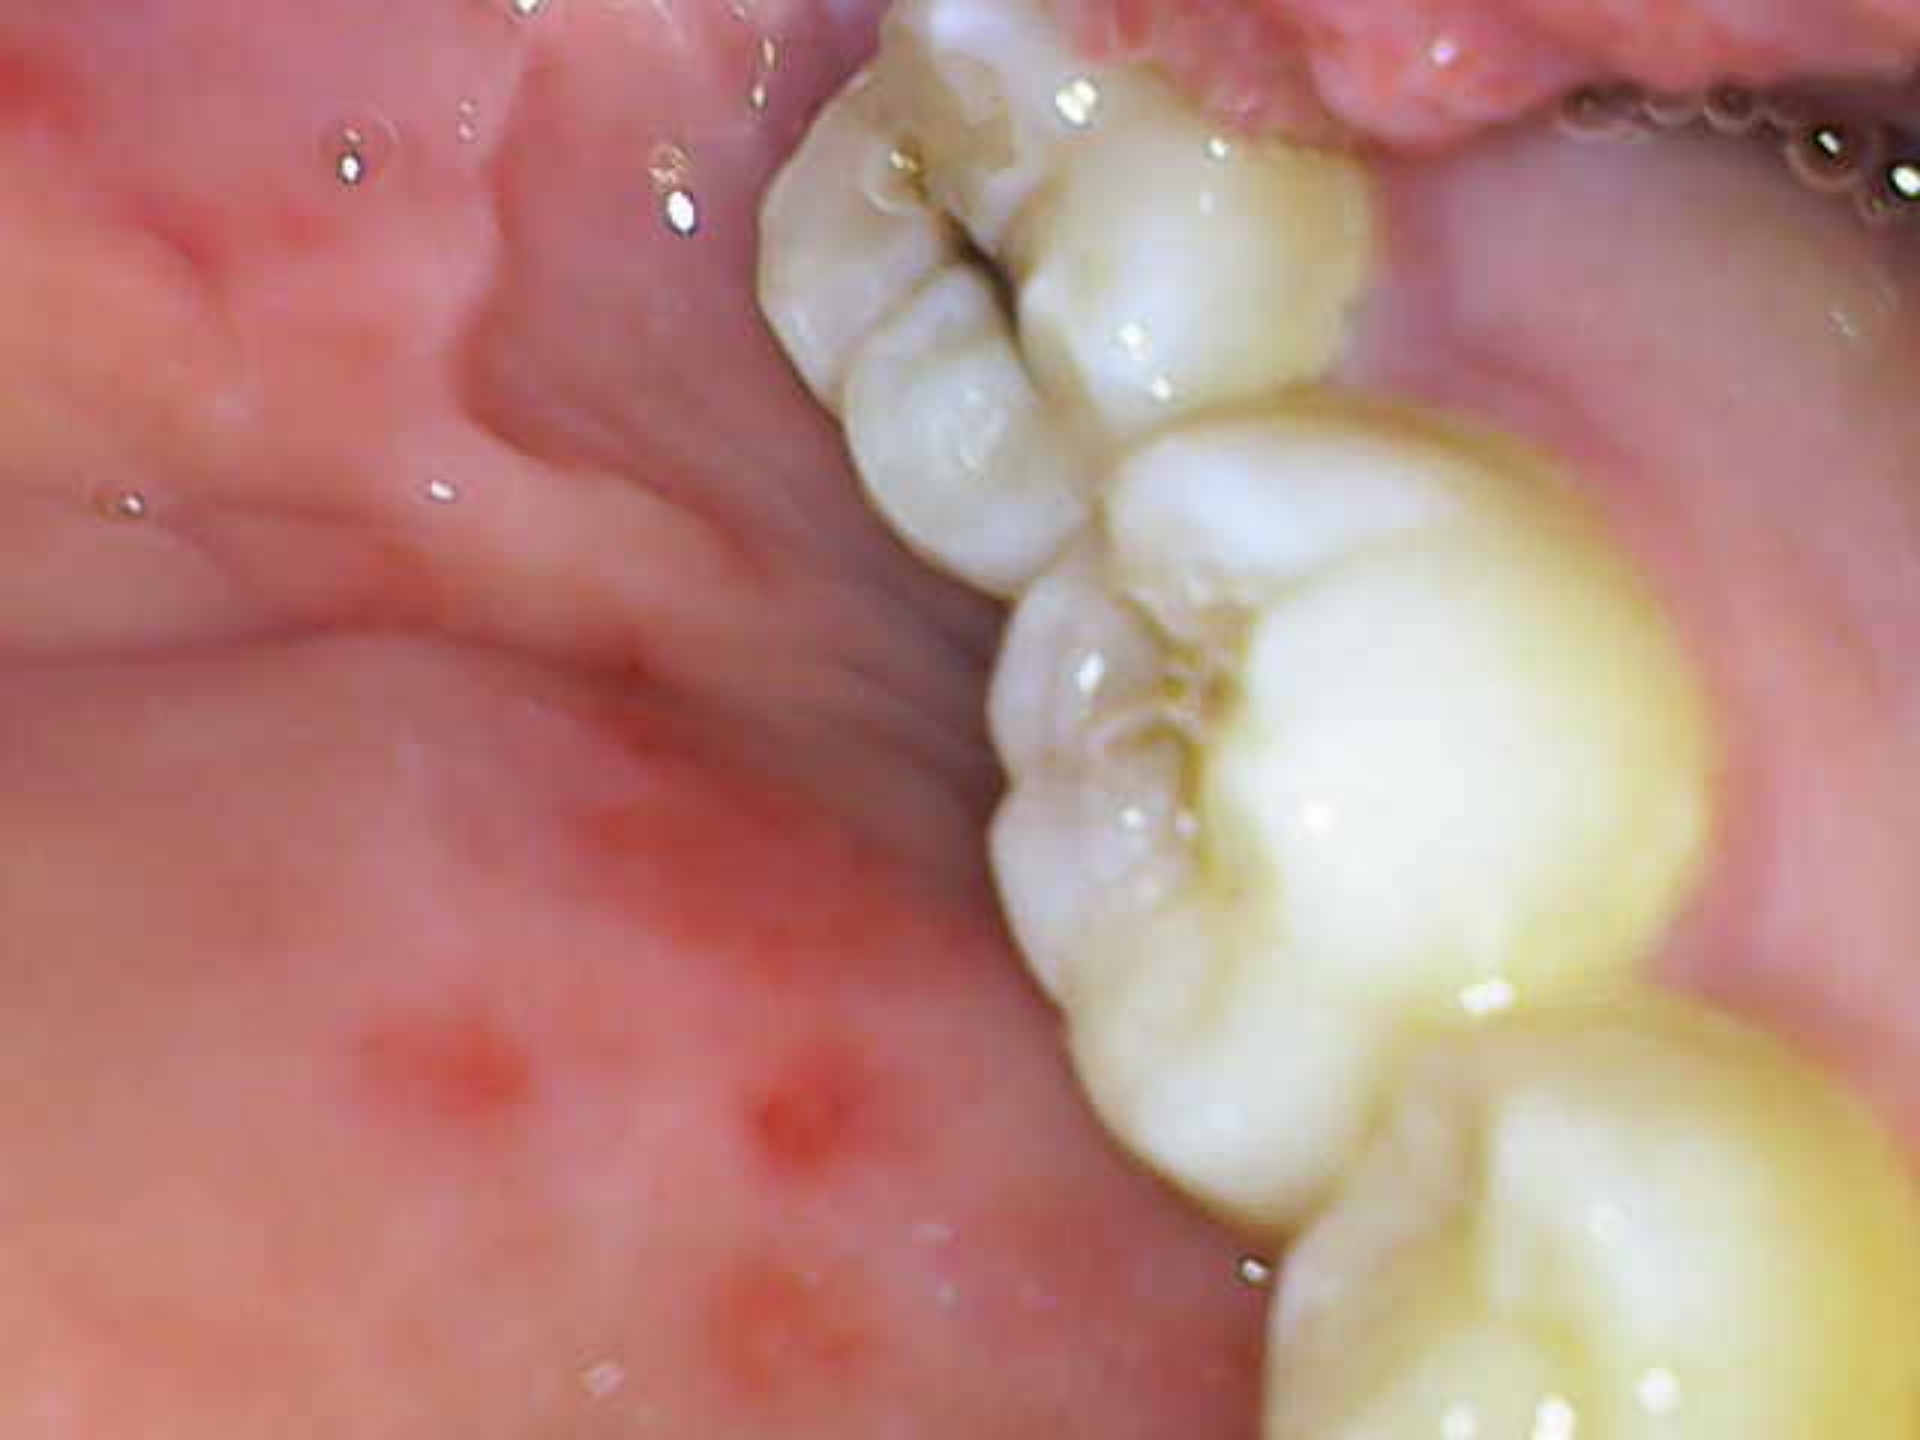

Удалял зубы мудрости, удаление сложное, резали десну, зашивали, сняли вчера швы.

После удаления первых двух прошло 4 недели. После удаления оставшихся - 2 недели. Дырочки, само собой еще не заполнились костью или чем там.

Когда мне можно будет ходить в тренажерный зал? Резких движений я там не делаю, но поднимаю тяжести.